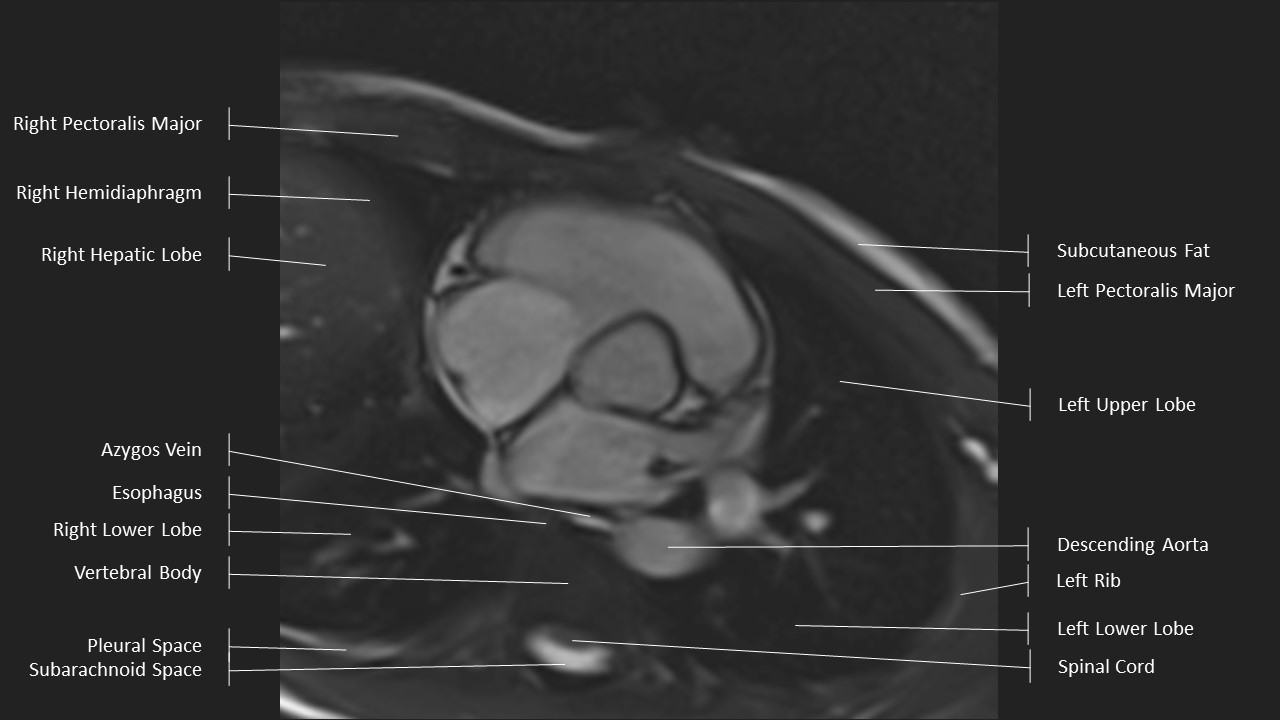

Short Axis Series

Axial Series